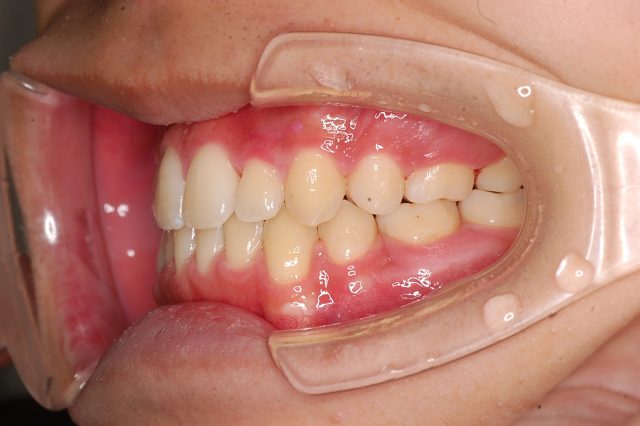

Before

After

主訴

前歯で噛めない

治療期間・回数

2年6ヶ月・30回

治療方法

マルチブラケットにて上下左右4本抜歯

費用

850000+税

デメリット・注意点

歯根吸収 歯肉退縮